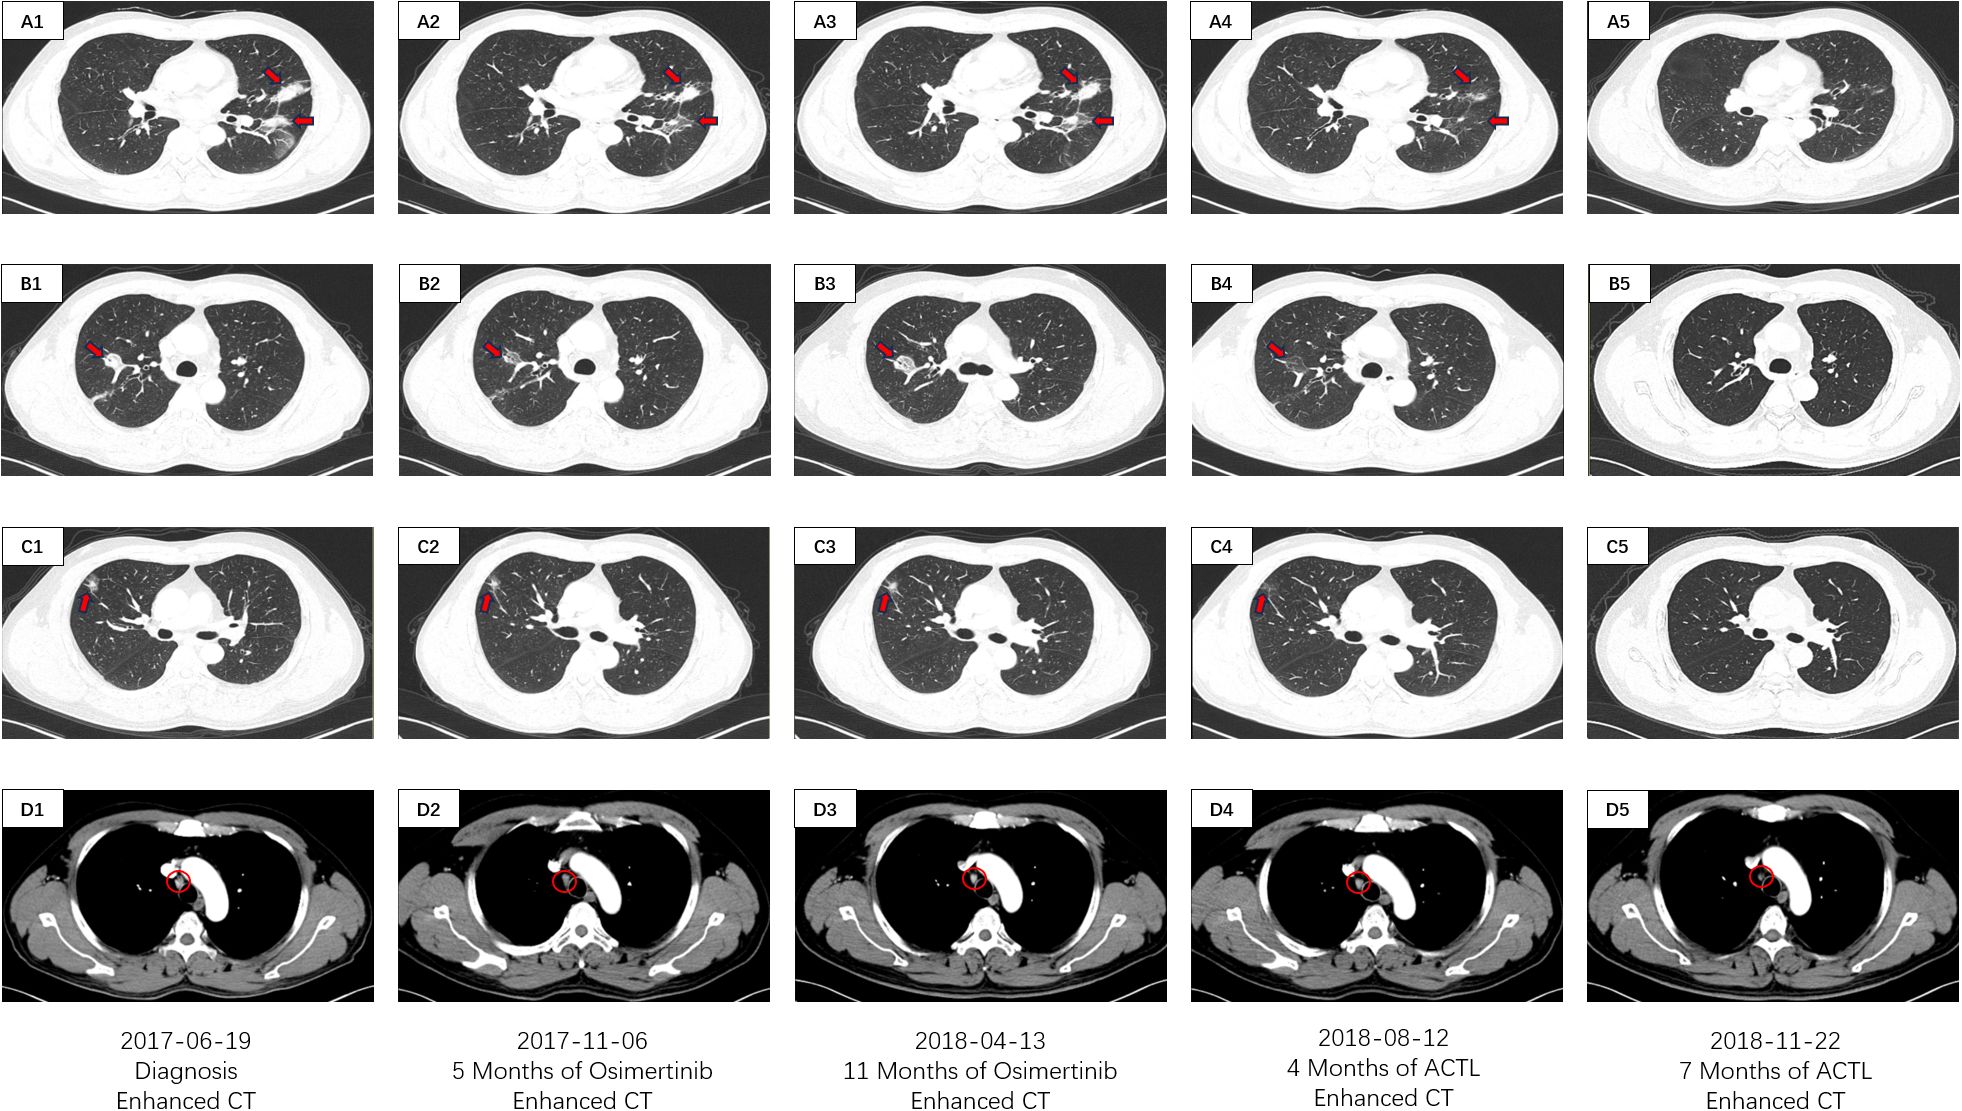

On June 19, 2017, a 53-year-old male patient presented with a 1-month history of persistent dry cough, intermittent expectoration of yellowish-white mucoid sputum, and nonspecific chest discomfort. The patient had no family history of malignant tumors, no smoking history, and no clear exposure history to environmental carcinogens. Laboratory tests indicated a significant inflammatory response: white blood cell count was 15.8×109/L (predominantly neutrophils), and C-reactive protein was 177.75 mg/L. Contrast-enhanced chest computed tomography (CT) revealed multiple intrapulmonary space-occupying lesions: a main lesion crossing the interlobar fissure in the left lung, a 39.4 mm×21.5 mm nodule in the upper lung closely adjacent to the interlobar fissure, with obvious traction on the lateral pleura, and a 41.5 mm×23.8 mm purely solid nodule in the lower lung with ground-glass cord shadows between it and the lateral pleura. A 25.3 mm×22.6 mm purely solid nodule in the inner zone of the right middle lung showed thickened and traversing blood vessels within the lesion, with obvious solid traction to the lateral pleura. A 20.4 mm×14.5 mm mixed ground-glass nodule in the outer zone of the right middle lung had surrounding spiculation signs. Additionally, an abnormally enlarged lymph node (16.3 mm×9.36 mm) was observed in the mediastinum. Bilateral multiple nodular opacities were present, with multiple local cord-like and grid-like changes, highly suggestive of diffuse pulmonary metastasis with mediastinal lymph node metastasis on imaging (Figures 1A1–D1). Systemic evaluation including contrast-enhanced abdominal CT, bone scan, and contrast-enhanced cranial magnetic resonance imaging (MRI) revealed no distant metastases. Tumor markers showed abnormally elevated CEA level at 13.25 ng/ml (reference range: 0–5 ng/ml) and CK-19 fragment (CYFRA21-1) level at 7.21 ng/ml (reference range: 0–3.3 ng/ml) (Figure 2A). Cytokine/lymphocyte subset testing showed that IFN-γ levels and CD4+/CD8+ ratio were within normal ranges (Figures 2B, C).

Figure 1. CT imaging assessment of lung lesions and mediastinal lymph node throughout the course of disease corresponding to their respective time points. (A1–D1) CT imaging of the lung window (A1–C1) and the mediastinal window (D1) on June 19, 2017; (A2–D2) CT imaging of the lung window (A2, B2, C2) and the mediastinal window (D2) on November 06, 2017; (A3–D3) CT imaging of the lung window (A3–C3) and the mediastinal window (D3) on April 13, 2018; (A4–D4) CT imaging of the lung window (A4–C4) and the mediastinal window (D4) on August 12, 2018; (A5–D5) CT imaging of the lung window (A5–C5) and the mediastinal window (D5) on November 22, 2018. (A1–5) images manifests the lesions of the left lobe in the CT lung window. (B1–5) images manifests the inner lesion of the right middle lobe in the CT lung window. (C1–5) images manifests the outer lesion of the right middle lobe in the CT lung window. (D1–5) images manifests the mediastinal lymph nodes in the CT mediastinal window.

The patient had poor baseline physical tolerance, and targeted therapy was chosen. Considering their driver gene mutation status, the third-generation EGFR-tyrosine kinase inhibitor (EGFR-TKI) osimertinib was ultimately determined as the first-line treatment regimen. In the early stage of treatment, the patient’s condition showed remission, and they self-reported improvement in cough and sputum symptoms. A contrast-enhanced chest CT on November 6, 2017, showed that each intrapulmonary lesion had shrunk to a certain extent, with solid components showing a “ground-glass-like” dissipating trend; the solid traction between the lesions and the pleura was also relieved to varying degrees. The lymph node shrank to 11.6 mm×8.1 mm (Figures 1A2–D2). The CEA level decreased to 9.24 ng/ml, and the CYFRA21–1 level decreased to 6.03 ng/ml (Figure 2A). This indicated that osimertinib treatment was effective.

However, the patient subsequently gradually complained again of aggravated cough and chest discomfort. A contrast-enhanced chest CT on April 13, 2018, showed that the lesions in the upper and lower lobes of the left lung had solid components expanding to varying degrees; the lesion in the inner zone of the right middle lobe showed significant expansion in scope and solidity. The size of the lymph node was similar to before, but the center was slightly more enhanced than before (Figure 1A3–D3). The CEA level rebounded again to 11.07 ng/ml, and the CYFRA21–1 level rose to 6.09 ng/ml (Figure 2A). Imaging progression, tumor marker rebound, and symptom deterioration collectively indicated the occurrence of acquired resistance to osimertinib. We performed tissue biopsy combined with NGS, and multiple EGFR-TKI resistance-related mutations including T790M, Mesenchymal-epithelial transition factor (MET) amplification, Kirsten rat sarcoma viral oncogene homolog (KRAS) mutation, small cell transformation-related genes, etc., were all negative, indicating that the patient had acquired EGFR-TKI resistance with unknown mechanisms. At the same time, the patient’s immune indices showed significant changes, with IFN-γ decreasing from the previous 11.2 pg/ml to 6.1 pg/ml (reference range: 0–17.2 pg/ml), and the CD4+/CD8+ ratio decreasing from 1.4 to 0.9 (reference range: 1–2.5) (Figures 2B, C). This indicated a state of low immune function and overall immune suppression at this time.

After ACTL treatment, the patient’s subjective symptoms improved. A contrast-enhanced chest CT just four months later showed surprising lesion resolution in multiple sites of both lungs. The lesions in the upper and lower lobes of the left lung shrank by 87% and 82%, respectively, with almost complete disappearance of solid components, leaving only partial ground-glass opacities, and the traction to the pleura disappeared. The solid components of the two lesions in the middle lobe of the right lung completely vanished, leaving only faint ground-glass-like contour shadows. The lymph node regressed to 9.21 mm×5.21 mm with reduced density (Figures 1A4–D4). Tumor marker levels decreased, with the CEA level dropping to 7.24 ng/ml and the CYFRA21–1 level decreasing to 5.14 ng/ml (Figure 2A). According to the Response Evaluation Criteria in Solid Tumors version 1.1 (RECIST 1.1) (8), this was determined as partial response (PR). Notably, the patient’s immune indices significantly improved simultaneously, with the IFN-γ level surging to 32.4 pg/ml and the CD4+/CD8+ ratio rising to 6.2, indicating that the body’s immune status had shifted from suppression to activation and from a previous low-functioning state to a high-functioning state (Figures 2B, C).

Treatment continued until November 22, 2018, when the patient’s symptoms completely disappeared. Contrast-enhanced chest CT showed that all lesions in both lungs had vanished; the lymph node shrank to a normal size of 4.02 mm×2.21 mm (Figures 1A5–D5). The CEA level was 4.12 ng/ml, and the CYFRA21–1 level was 3.45 ng/ml (Figure 2A). According to the RECIST 1.1 criteria, this was judged as clinical complete response (cCR). The follow-up has lasted more than 6 years to date. Imaging remains normal with no evidence of recurrence or progression, and tumor markers have remained normal, with CEA at 2.85 ng/ml and CYFRA21–1 at 2.52 ng/ml on April 22, 2024 (Figure 2A). The patient has maintained a stable and long-term cCR status. This case demonstrates the remarkable efficacy of ACTL cellular immunotherapy in advanced lung cancer patients with EGFR-TKI acquired resistance, providing new treatment insights for similar refractory cases.